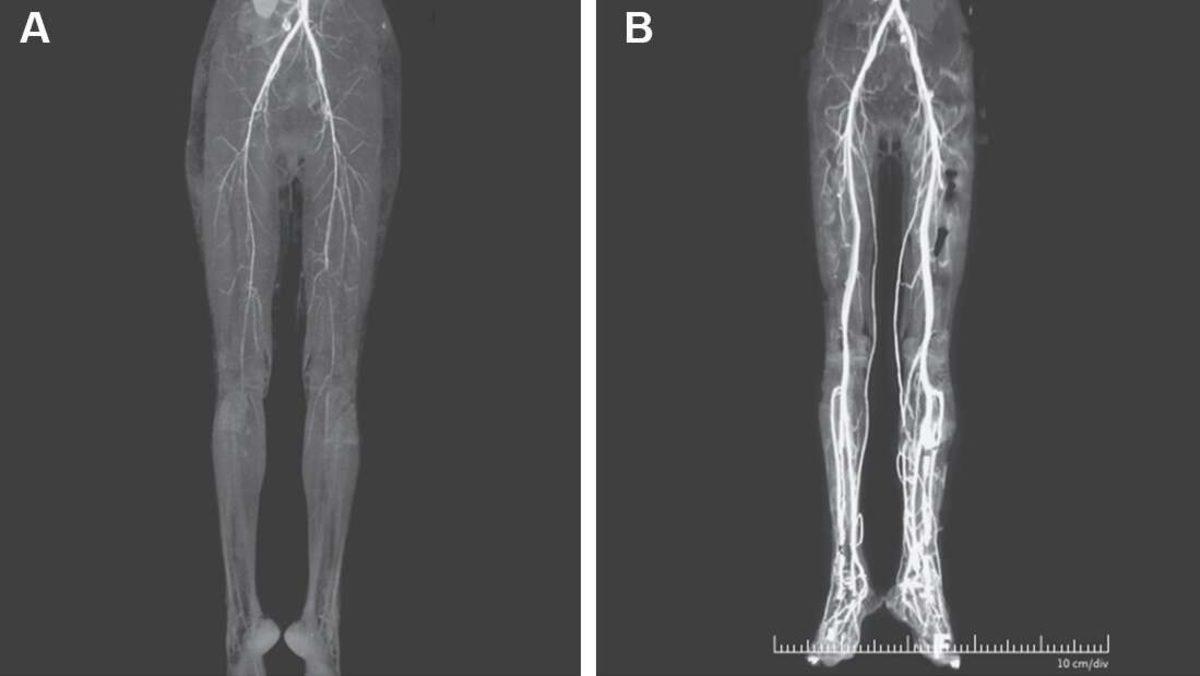

Derhal tedavisine başlanan kadının, alt bacaklarında ve ayaklara kan pompalayan atar damarlarında nabız olmadığı anlaşılmış. Bunun üzerine kadın üzerindeki incelemelerini daha da derinleştiren doktorlar, heparin tedavisine başladılar. Kanın inceltilmesini sağlayan heparin, kadının bacaklarındaki ağrının azalmasını sağlamış. Bu süreç içerisinde kadının ayakları yeniden ısınmaya başlamış olsa da ayak parmaklarından biri kangren olduğu için kesilmek zorunda kalınmış.

Son olarak doktorlar, kadının ergotizm nedeniyle St Anthony ateşi hastalığına yakalandığına kanaat getirdiler. Ortaçağ'da, özellikle Avrupa'yı kasıp kavuran bu hastalık, günümüzde neredeyse hiç görülmüyor. Bu nedenle bir kadında yeniden bu sancılı hastalığın görülmesi, doktorların kadını daha yakından incelemesine neden oldu.